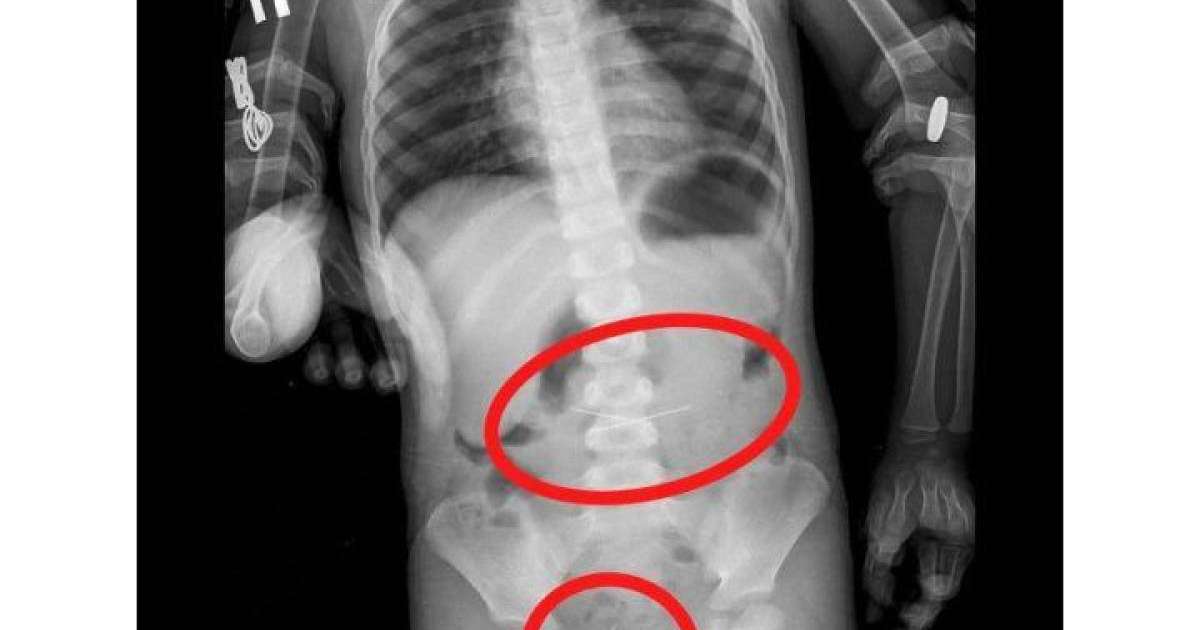

Баланың іш қуысының шолу рентгенографиясында дәрігерлер жүгіргішті және асқазанның проекциясында екі тігін инесін анықтады. FGDS процедурасы кезінде олардың біреуі алынып тасталды.

Бала бақылауда болды. Көп ұзамай дәрігерлер іш қуысының R-граммында жамбас проекциясында төртінші инені тапты. Колоноскопия жасалды және сигма тәрізді ішектен соңғы ине алынып тасталды. Қазіргі уақытта баланың жағдайы бірқалыпты.